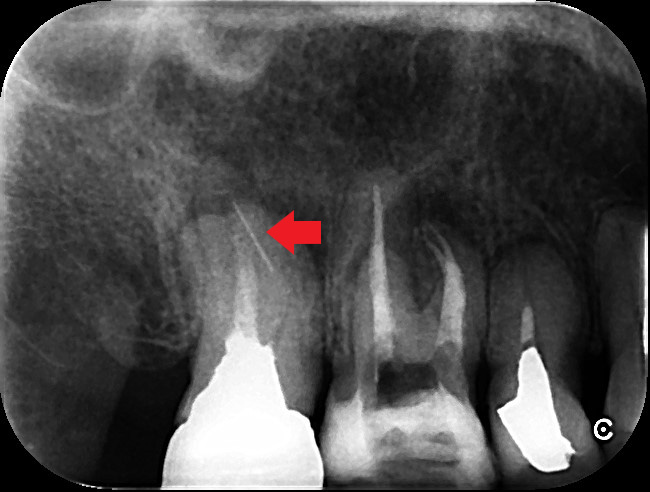

歯根の先に大きな膿があり、再根管治療が必要ですが破折ファイルが根管を塞いでいます。根管治療で膿を改善するためには、破折ファイルを除去し根管の殺菌・消毒が必要です。破折ファイルは除去が難しいケースもあり、必要に応じて外科的歯内療法を選択することもあります。本ケースは、手術なしで破折ファイルを除去し、再根管治療により大きな膿を改善しました。

破折ファイルがあり、根の先に膿がみられる場合は破折ファイル除去が必要になります。破折フィル除去には歯科用顕微鏡とCTスキャンがあると、安全にかつ確実な除去をしやすくなります。